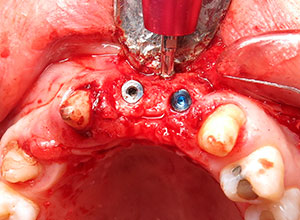

Se espera de 6 a 8 meses para lograr la integración del injerto, se descubre el área para la colocación de implantes dentales.

Se observa la integración de los implantes, en algunos casos se puede dejar los tornillos de fijación, bien integrados. El paciente está listo para la rehabilitación protésica.